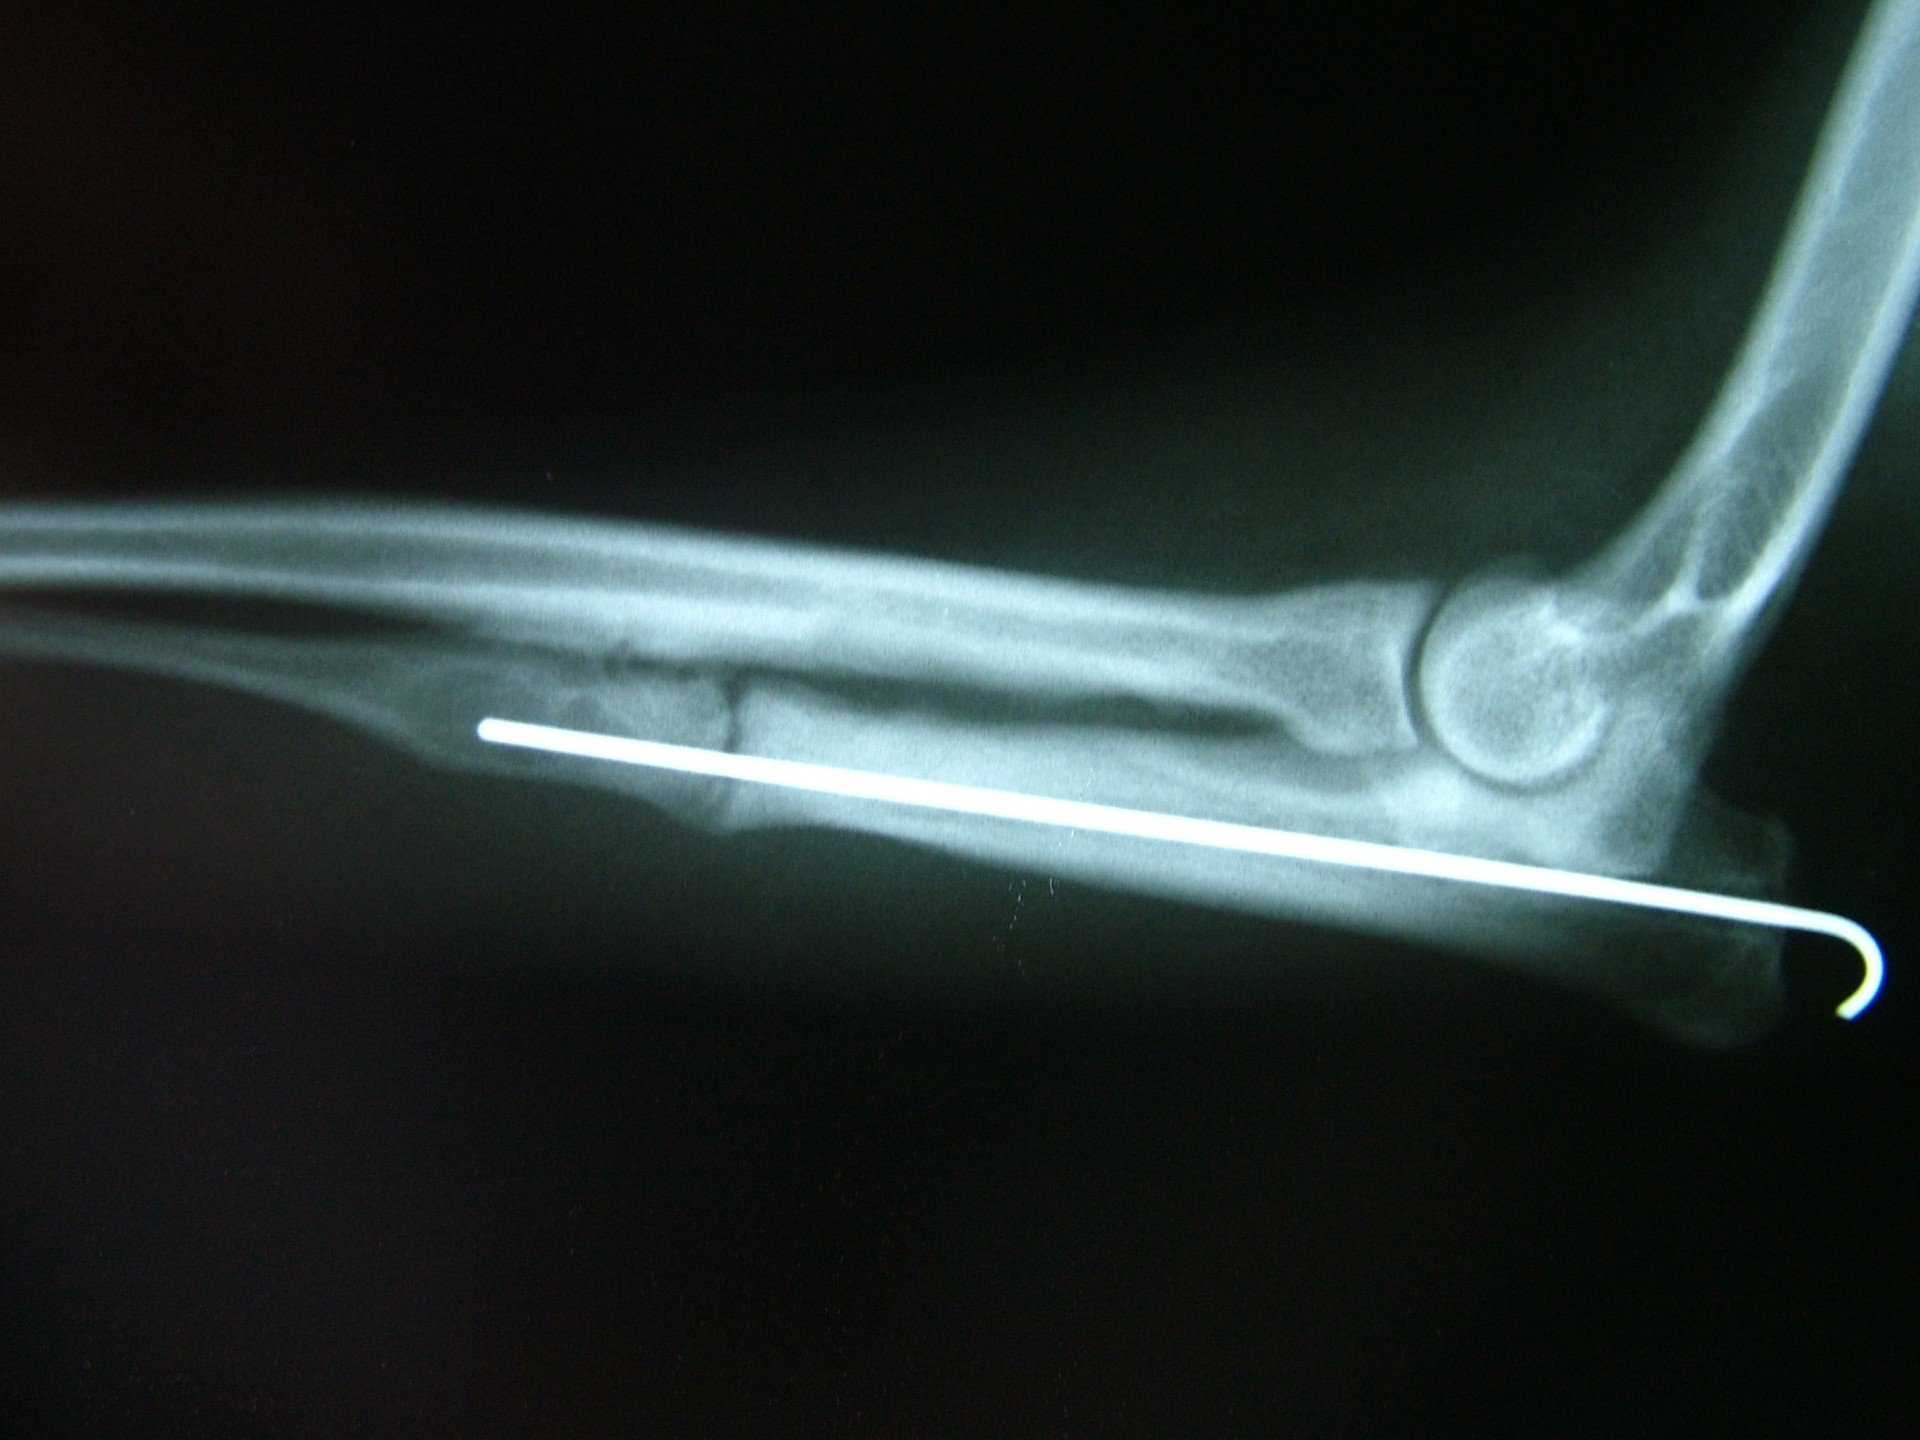

Az alkarcsont növekedési zónájának záródása általában a könyökízületben un.: inkongruenciát okoz. A könyökízület működéséhez az azt alkotó 3 csont (karcsont, könyökcsont, alkarcsont) tökéletes illeszkedése elengedhetetlen. Azokban az esetekben amikor bármely 2, a könyökízület alkotásában résztvevő csont ízületi felszíne nem illeszkedik tökéletesen,rendellenes ízületi alakulásról, inkongruenciáról beszélünk. Ezekben az esetekben az ízületi felszínek nem megfelelő terhelődése azok kopásához, idült ízületgyulladáshoz, következményesen fájdalomhoz vezet.

Az alkarcsont alsó vagy felső növekedési zónájának lezáródása esetén a könyökízületben kialakuló inkongruencia az ízület mozgásának fájdalmasságához, a mozgáspálya beszűküléséhez vezet. Paradox módon az ilyen elváltozás esetén is (mivel az alkarcsont a teherviselő csont) a könyökcsont osteotomiájával, annak növekedésének korlátozásával gyógyítjuk a beteget.

Az idejében észrevett elváltozás esetén, - amennyiben a csövescsontok növekedése még nem állt le -, az ízület normalizálódik, az eredeti funkció visszaáll.Súlyos fokú inkongruencia kialakulása esetén az ízületi funkció már nem állítható vissza. Azokban az esetekben, amikor a súlyos ízületi elváltozás fájdalommal jár az ízület bemerevítésével (arthrodesis) a fájdalom megszüntethető.